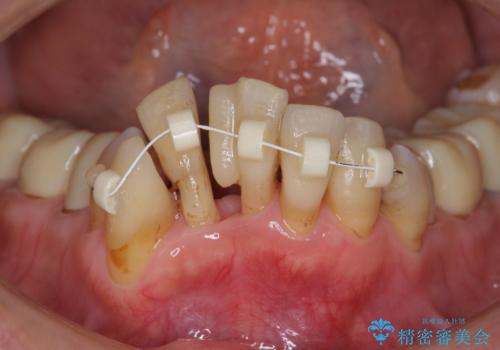

- 上顎前歯の黒ずみの改善、下顎前歯の十度なガタつき、矯正治療とセラミック治療を含む全体的な治療を希望され来院されました。

銀歯を高強度の仮歯に替えたのち、下顎前歯のみの部分矯正→全体的なマウスピース矯正治療(インビザライン)→最終的なセラミック治療と治療を進めます。

矯正治療と目立つ銀歯のやりかえを行ったことでかみあわせだけでなく、審美性・清掃性も改善し口腔内の環境を劇的に改善することができました。